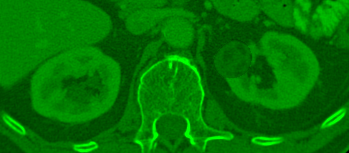

Green Channel: Density Extremum

Green Channel Image

Density Extremes

Captures extreme tissue densities outside the standard clinical view, crucial for identifying fatty tissues and calcifications.